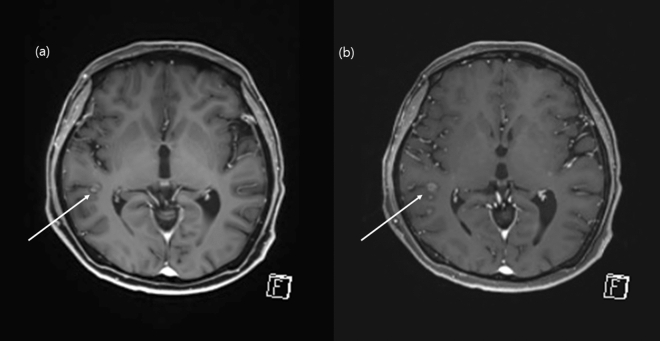

We demonstrated that the contrast-enhanced CS-VIBE may be a feasible and reliable accelerated MR method for the detection of enhancing intracranial lesions (Figs. 5 and 6). Both MPRAGE and VIBE are known to provide T1-weighted images and use spoiled GRE sequences with ultrashort TRs8. MPRAGE requires a prolonged scan time due to the extended magnetization preparation and recovery time before rapid GRE acquisition. On the other hand, VIBE utilizes a fast low-angle shot approach to produce T1-weighted image contrast in steady state imaging. In addition, the VIBE is superior in contrast-enhancement as the short TR of VIBE could increase the SNR and CNR of enhancing lesions8,9. Previous studies found that contrast-enhanced VIBE sequence was an effective, alternative approach to MPRAGE imaging for 3D T1-weighted imaging of the brain which demonstrated superior lesion detection and lesion conspicuity8,9. In this study, we applied CS to further accelerate brain imaging. CS has been used in clinical settings to combine incoherent k-space sampling during acquisition with a dedicated iterative reconstruction algorithm22. Although several studies have shown that the CS technique is useful for reducing the scan time when evaluating the vessel walls or neurovascular compression syndrome18,23,24, CS-VIBE has not been used in various sequences other than the dynamic imaging of the liver or breast with a high spatio-temporal resolution10,11,25. Although we previously found that accelerated CS-VIBE MRI could be a reliable method for the diagnosis of facial neuritis with half the scan time of conventional MPRAGE, the application of CS-VIBE to the CNS remains limited15.

Figure 5.

Comparison of an enhancing intracranial lesion on conventional MPRAGE and CS-VIBE. A 52-year-old female with intracranial metastasis from lung cancer. A tiny nodular rim-enhancement in the right temporal cortex indicated intracranial metastasis. Both conventional MPRAGE (a) and CS-VIBE (b) showed a similar shape and enhancement; however basal ganglia structures and white gray matter differentiation were clearer with conventional MPRAGE.